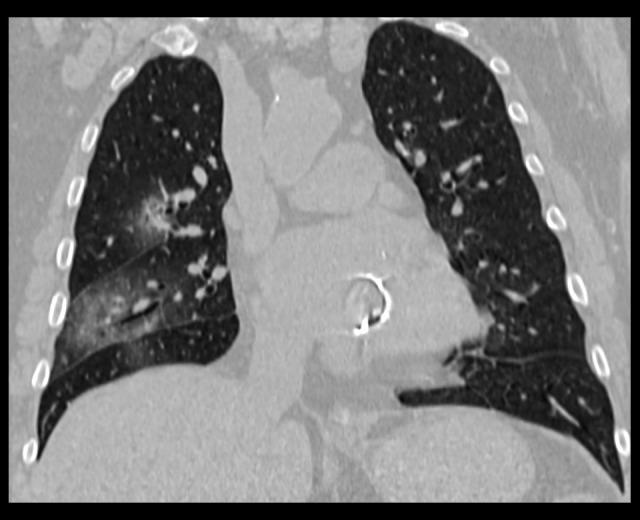

BACKGROUND Chest imaging may be taken into consideration in detecting viral lung infections, especially if there are no tests available or there is a need for a prompt diagnosis. Imaging modalities enable evaluation of the character and extent of pulmonary lesions and monitoring of the disease course. The aim of this study was to verify the prognostic value of chest CT in COVID-19 patients. MATERIAL AND METHODS We conducted a retrospective review of clinical data and CT scans of 156 patients with SARS-CoV-2 infection confirmed by real-time reverse-transcription polymerase-chain-reaction (rRT-PCR) assay hospitalized in the Central Clinical Hospital of the Ministry of the Interior in Warsaw and in the Medical Centre in Łańcut, Poland. The total severity score (TSS) was used to quantify the extent of lung opacification in CT scans. RESULTS The dominant pattern in discharged patients was ground-glass opacities, whereas in the non-survivors, the dominant pulmonary changes were consolidations. The non-survivors were more likely to have pleural effusion, pleural thickening, lymphadenopathy, air bronchogram, and bronchiolectasis. There were no statistically significant differences among the 3 analyzed groups (non-survivors, discharged patients, and patients who underwent prolonged hospitalization) in the presence of fibrotic lesions, segmental or subsegmental pulmonary vessel enlargement, subpleural lines, air bubble sign, and halo sign. CONCLUSIONS Lung CT is a diagnostic tool with prognostic utility in COVID-19 patients. The correlation of the available clinical data with semi-quantitative radiological features enables evaluation of disease severity. The occurrence of specific radiomics shows a positive correlation with prognosis.

出院患者的主要表现为磨玻璃影,而未存活患者的主要肺部改变为实变。未存活患者更有可能出现胸腔积液、胸膜增厚、淋巴结病、空气支气管征和支气管扩张。在 3 个分析组(未存活患者、出院患者和住院时间延长的患者)中,纤维化病变、肺段或亚段血管扩大、胸膜下线、气液征和晕征的存在无统计学差异。